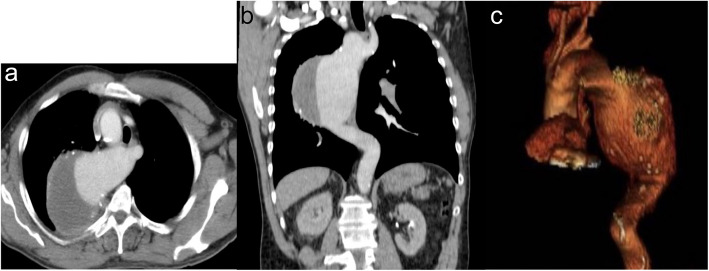

Case presentation: Α 55 year old patient was admitted in our hospital with chest pain. After the initial clinical and laboratory workout that was negative for acute coronary syndrome, Computed Tomography Angiography revealed an aneurysm of the descending aorta 10,3 cm in width, and a right sided aortic arch (Edwards' classification). Endovascular repair was selected as the treatment option of choice. Technically the endografting was challenging, firstly because of the right sided aortic arch, secondly because the four aortic branches originate independently. In order to identify the orifices of arch vessels during the angiography, brachial access in both upper extremities was achieved. In this way, it was possible to correctly deploy the thoracic aortic stent graft. No endoleaks were observed in the final angiography. Postoperative Computed Tomography Angiography 10 months after the operation showed no endoleaks.